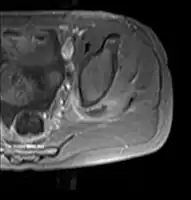

- Axial T1 weighted fat suppressed post IV gadolinium contrast enhanced MRI image showing a mutliloculated bacterial abscess in the left gluteal muscle which grew Staphylococcus aureus (methicillin sensitive) thought to be due to tropical pyomyositis.